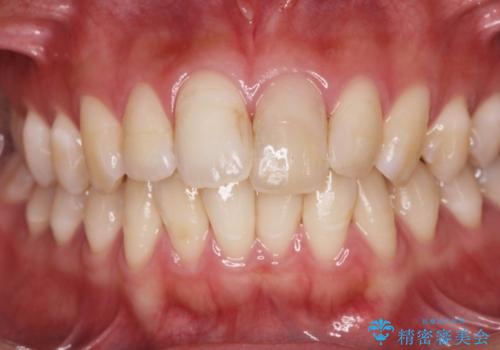

歯科技工士との綿密な打ち合わせで、非常に自然なセラミッククラウンを作製することができました。